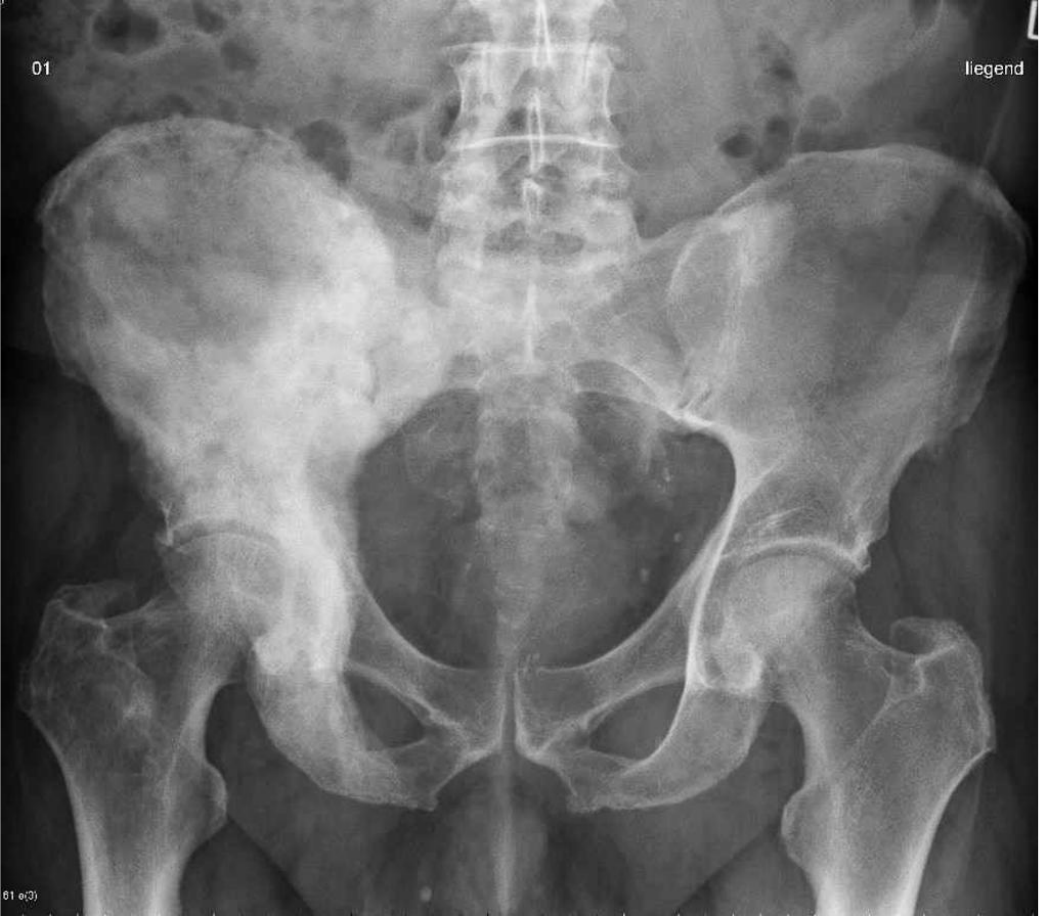

Observe a imagem abaixo e marque a opção que descreva corretamente os critérios

radiográficos que caracterizam a patologia.

Fonte: http://www.radiopaedia.org/cases/14072

sinal de "algodão": espessamento cortical e esclerose periosteal, com

aspecto "macio"

sinal de "mosaico", com padrões opacos bem definidos sobre uma área

lítica

sinal de "grama", com aspecto lucente ascendente no lado direito

sinal de "moldura", com áreas hipodensas na região do sacro e trocânter

maior direito

sinal de "algodão", com espessamento cortical e áreas osteolíticas bem

definidas

Explicação:

O sinal de "mosaico" produz aspectos mais uniformes e retilíneos, mesclando

áreas osteolíticas com áreas hiperdensas. O sinal de "grama" ocorre apenas

quando a doença acomete ossos longos. O sinal de "moldura" afeta apenas os

corpos vertebrais com áreas hiperdensas (opacas). O aspecto de "algodão"

caracteriza uma área hiperdensa, com espessamento sobre uma área lítica, o

que dá um aspecto irregular e compacto, como tufos macios de algodão.